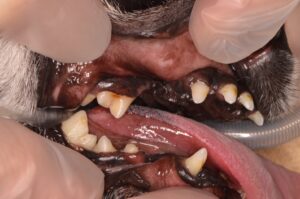

処置前の写真です。見た目の上では軽度の歯石に見えますが…

診察時、歯の表面上の歯石は少なく見えましたが一部歯肉が赤く腫れているところや本来の位置よりも下がっている歯肉も見られたため、見えない部分の詳細な診断や治療のため、麻酔をかけての検査・治療に進みました。